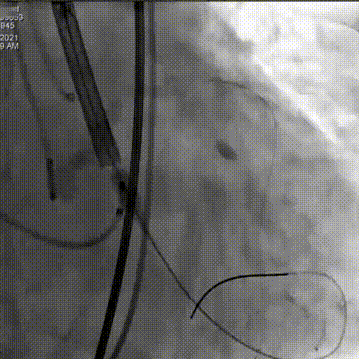

预置LCA保护